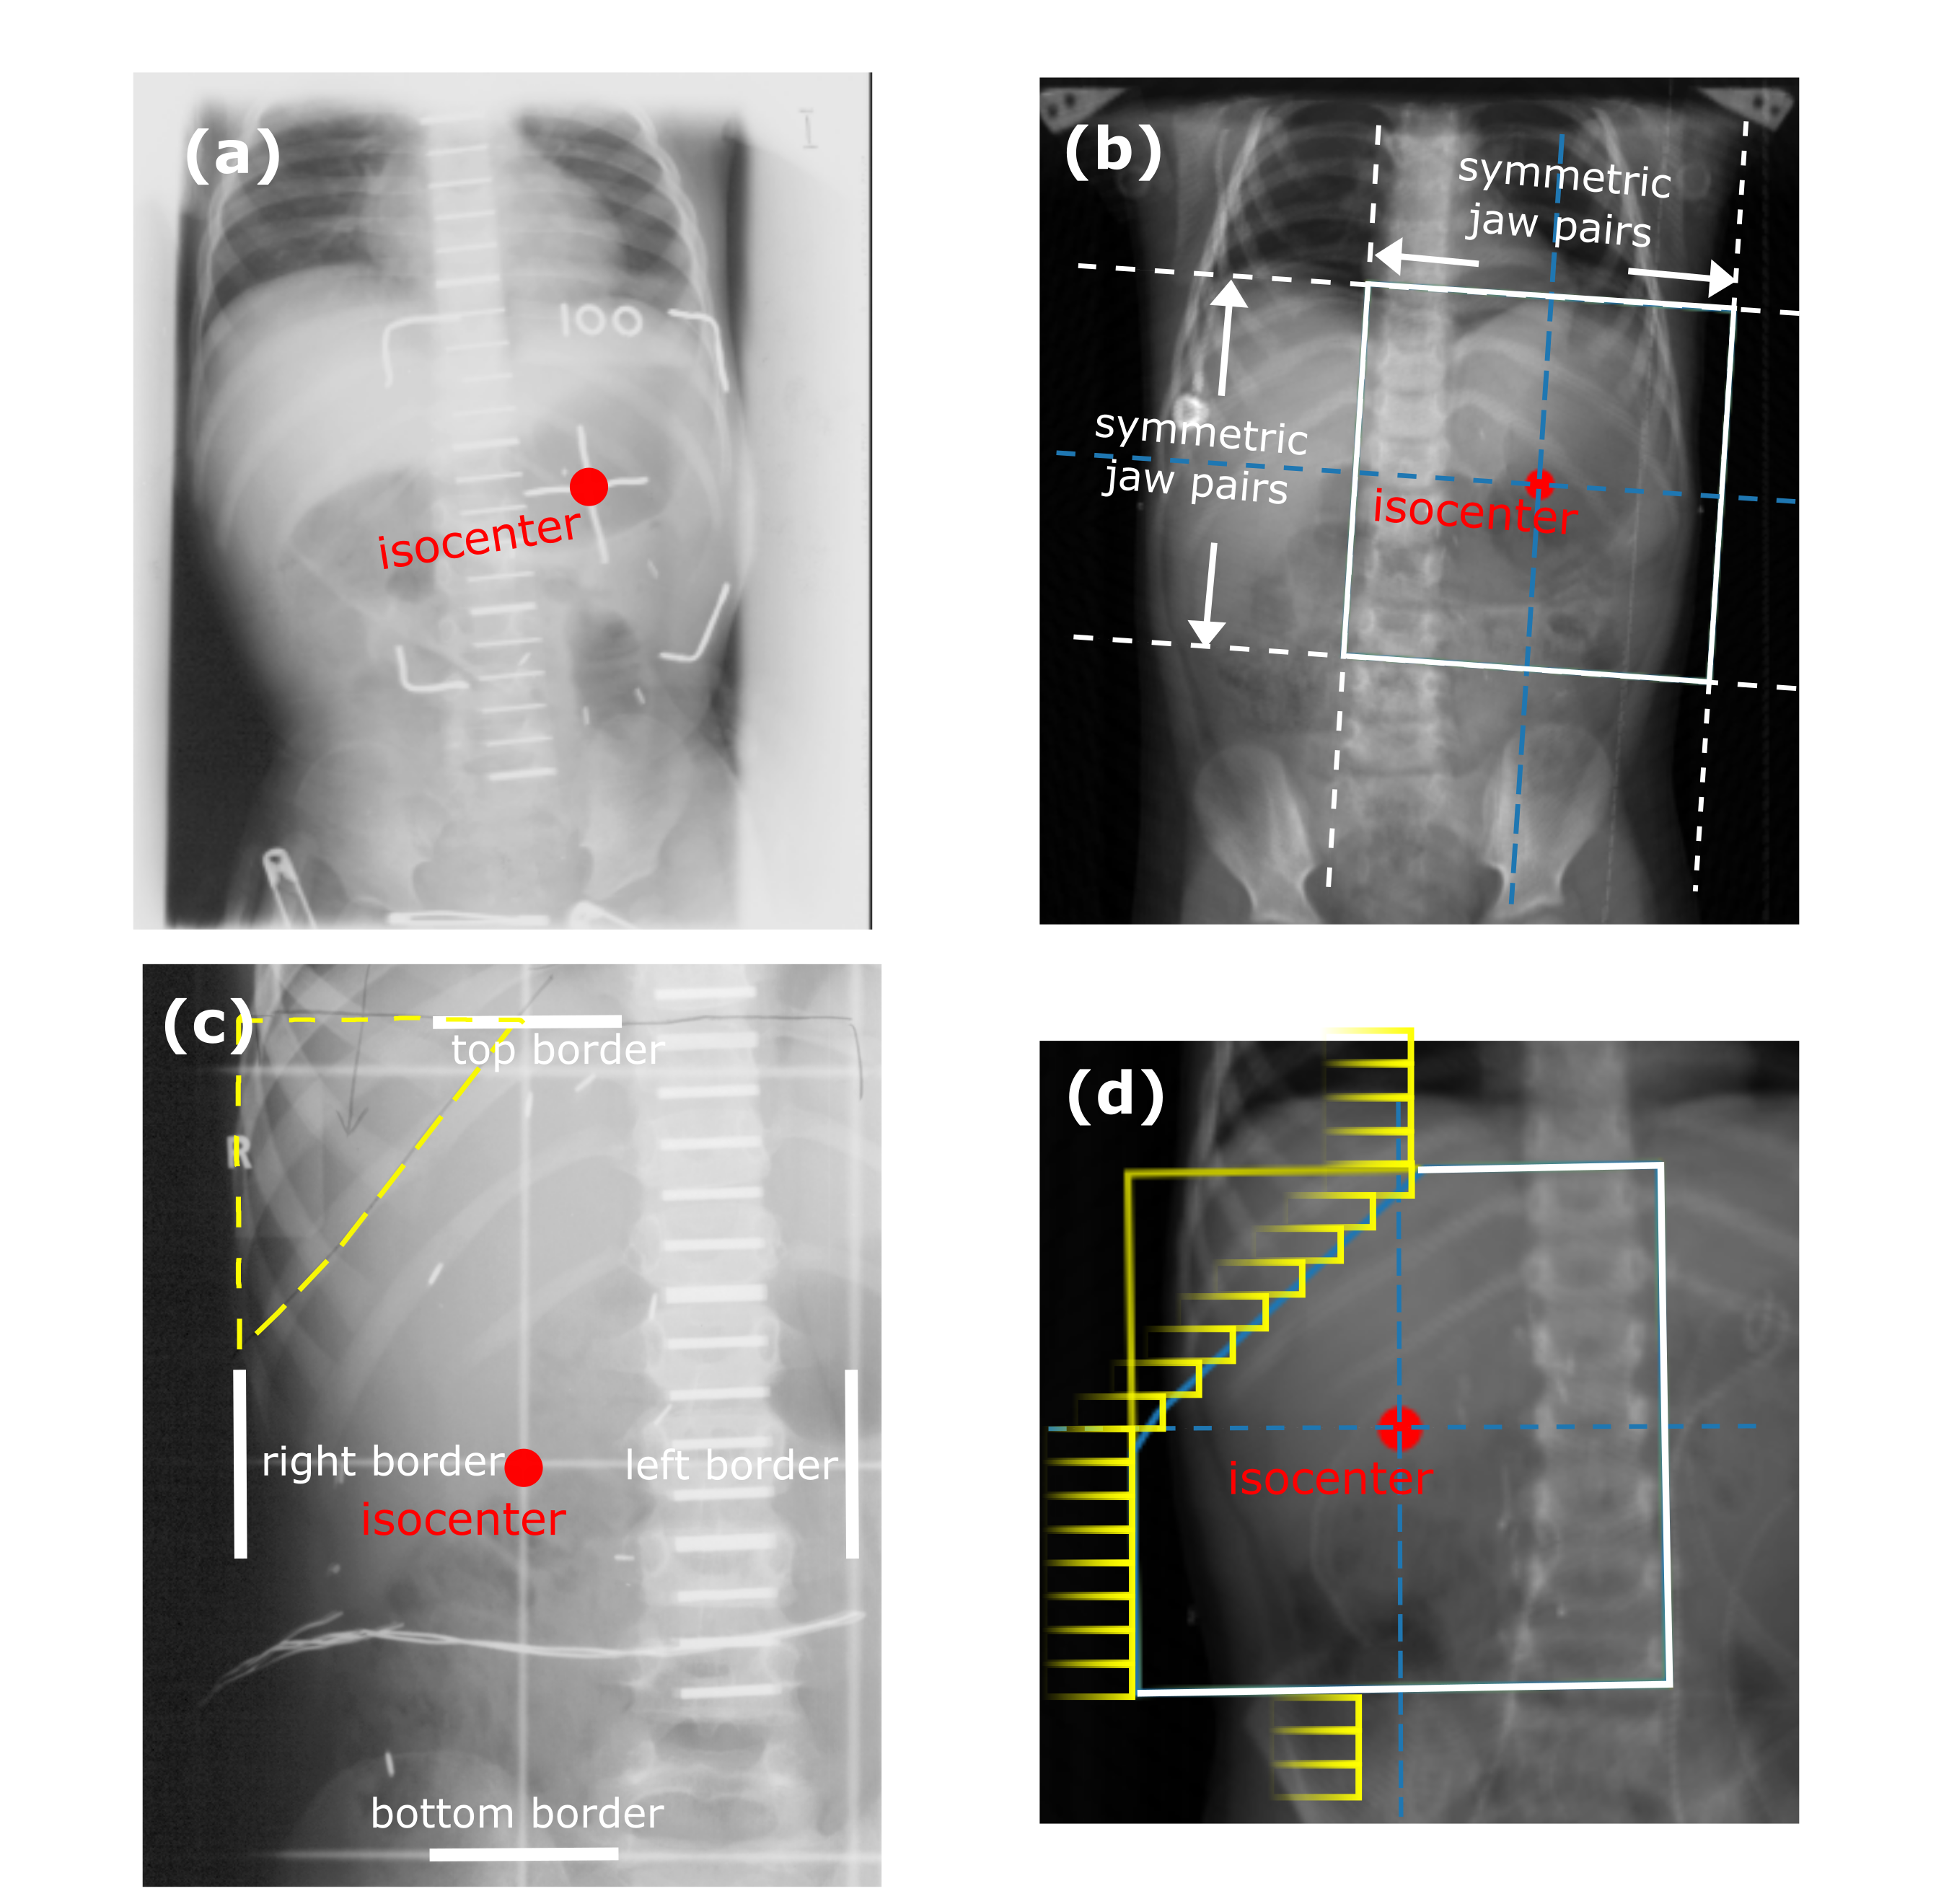

Figures 1(a) and 1(c) illustrate examples of actual historical plans on respective historical radiographs. As can be observed, a typical historical flank irradiation field is a rectangular area, with possible shielding blocks, that is located on the right or on the left flank. Irradiation is done by beams from anterior-posterior (AP) and posterior-anterior (PA) direction. Along right-left (RL), one field border is located at the edge of the patient’s body contour, while the other is located as to include the vertebral column (?). In some cases, blocks are placed to protect OARs from irradiation (Fig. 1(c)). In historical plans the isocenter is positioned in the center of the treatment field that is projected on the coronal plane (Fig. 1) and at the middle of the patient’s AP abdominal diameter.

For each plan generated, an additional version of that plan including one block was generated as well. A block was simulated as the area in the upper lateral corner enclosed by the border of the rectangular field and a line crossing two randomly sampled endpoints. The endpoints were sampled from two regions roughly covering the start and end points of rib 9 and rib 12 on the DRRs (regions indicated by the green boxes in Fig. 2). This way, a sampled block covered part of the liver (in right-sided plans) or part of the spleen (in left-sided plans). All plans consisted of two opposing and symmetrical beams in AP-PA directions irradiating one side of the abdominal flank. Figures 1(b) and 1(d) illustrate two examples of sampled artificial plans (without or with a block) on respective DRRs.